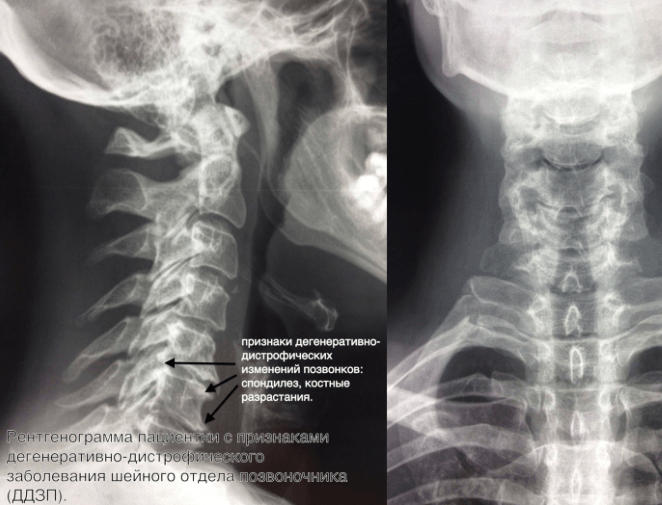

Медицинские снимки: рентген позвоночника сбоку